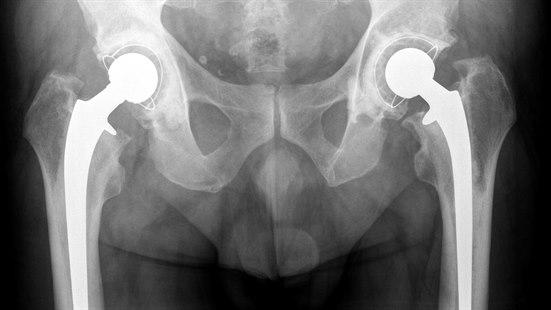

Total hofteprotese, kunstig hofteledd

Innsetting av en totalprotese i hofteleddet innebærer at både lårbeinshodet og hofteskålen erstattes med kunstige protesedeler. Gode forberedelser før inngrepet og riktig opptrening etter inngrepet bedrer prognosen.

En total hofteprotese innebærer at både lårbeinshodet og hofteskåla skiftes ut med kunstige deler av henholdsvis metall og plast.

Operasjonen Innsetting av total hofteprotese består i å erstatte lårbeinshodet med et metallhode og i tillegg skifte ut hofteskålen. Metallhodet er støpt sammen med et metallskaft som passer inn i lårbeinet. En plastskål festes til hoftebeinet (pelvis) og erstatter hofteskålen. Protesedelene, som er svært like de beindelene som erstattes, vil fungere som et normalt hofteledd.

Det finnes ulike varianter av kunstige hofteledd. Minst 19 av 20 hofteproteser som brukes i Norge (≥ 95%), har god dokumentasjon på kvalitet og holdbarhet. De øvrige er ofte nye modeller eller videreutvikling av eksisterende proteser, som fortsatt er under evaluering. Vanligvis er det kirurgen som foreslår hvilket hofteledd som egner seg best for den enkelte pasient. Materialene som protesene er laget av, er en kombinasjon av holdbare, slitesterke materialer som rustfritt stål, titanium, andre metaller, polyetylen og noen ganger keramikk. Det kunstige hofteleddet blir akseptert av kroppen, og protesen er laget for å motstå korrosjon, nedbrytning og slitasje i størst mulig grad.